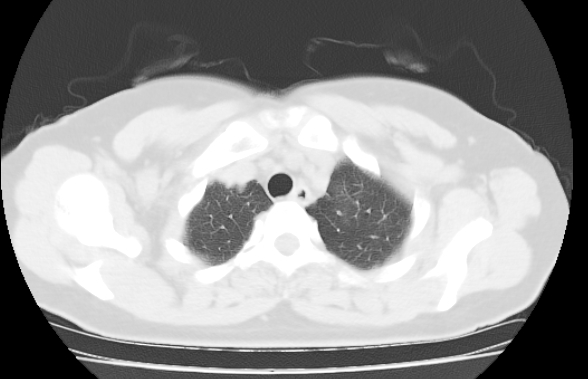

标题: CT25227:背部疼痛伴双侧胸壁痛2月,食欲差。 [打印本页]

标题: CT25227:背部疼痛伴双侧胸壁痛2月,食欲差。

肺结核并胸椎结核?请各位高手指教。

用椎体的条件来扫胸椎呀!考虑1左侧胸膜小结节形成2椎体结核并冷脓肿形成

左肺结核灶,胸椎结核并冷脓肿。

左肺结核灶,胸椎结核并冷脓肿